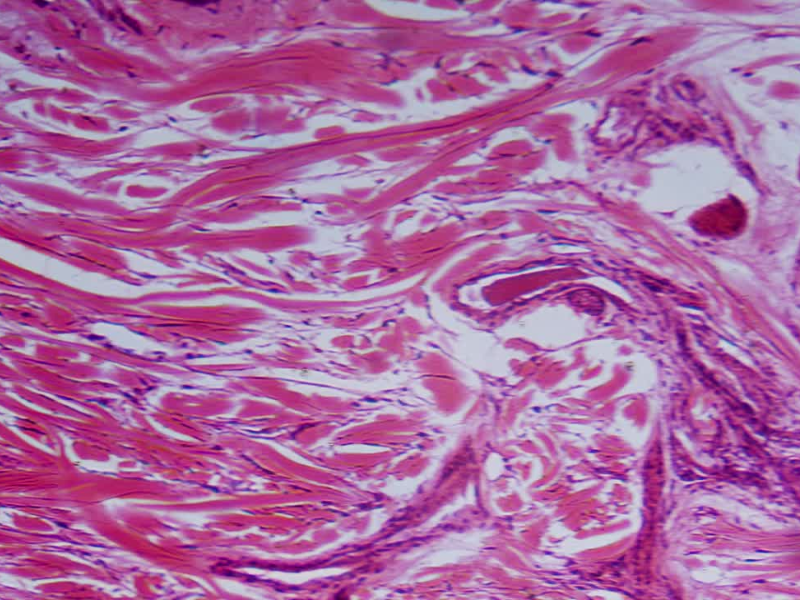

Nano Collagen Peptide – Tái tạo mô buồng trứng

Nguồn gốc: Collagen peptide thủy phân kích thước nano

Hoạt chất: Gly–Pro–Hydroxyproline\

Ohara, H., Ichikawa, S., Matsumoto, H., Akiyama, M., Fujimoto, N., Kobayashi, T., & Sato, K. (2010). Collagen peptide improves elasticity and tissue repair. Journal of Nutritional Science.

Kết quả: Hỗ trợ cấu trúc buồng trứng khỏe, cải thiện mô liên kết